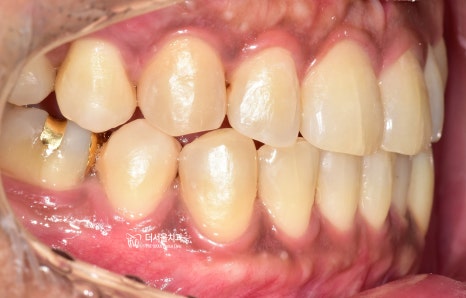

보기 좋은것도 좋은건데,

교합 기능의 올바른 부여로

음식을 더 잘 씹어드릴 수 있게 되셨네요.

끝으로, 이제 안모와의 중심선도

같이 일치 되는 것을 볼 수 있습니다.